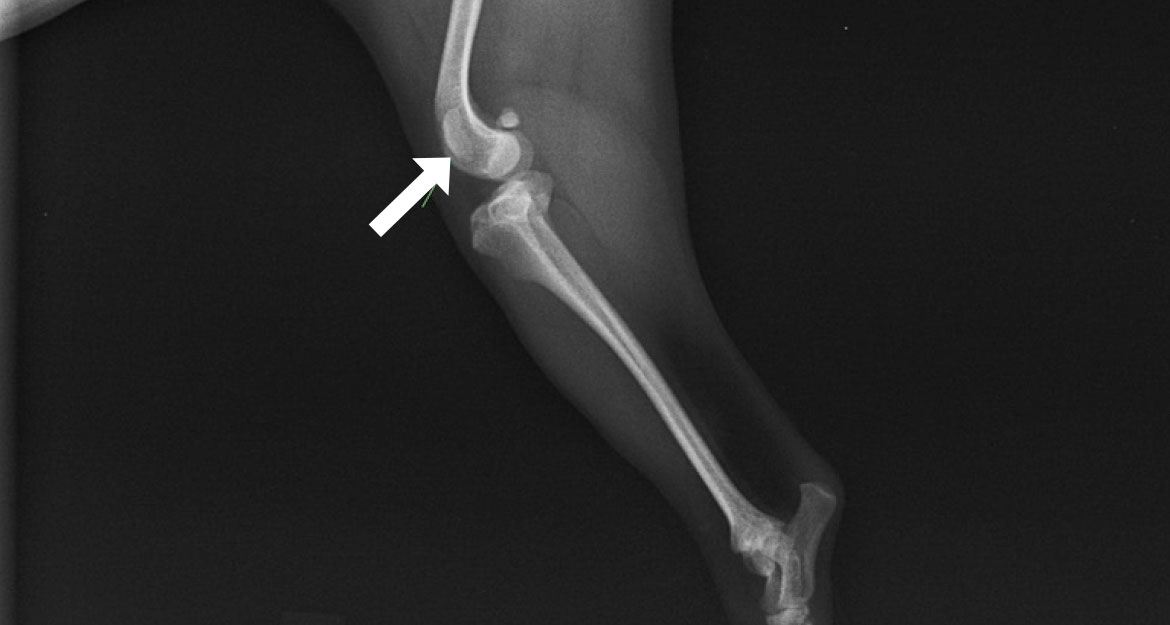

内方脱臼(右後肢)

-

Before

膝蓋骨が内側(内方)に変位しています -

After

膝蓋骨が正常な位置(正中)に整復されています